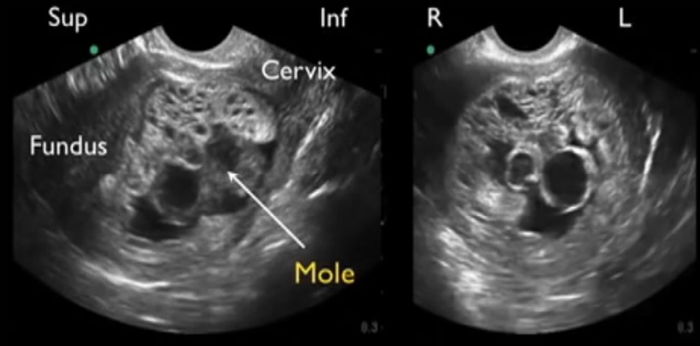

Hamil molar atau disebut juga hamil anggur adalah hasil kesalahan genetik selama proses pembuahan sehingga tumbuh menjadi jaringan abnormal di dalam rahim. Jaringan di rahim menjadi tumor, bukan menjadi plasenta.

Kehamilan molar lengkap hanya memiliki plasenta (tidak ada bayi) dan terbentuk ketika sperma membuahi sel telur kosong. Karena telur itu kosong, maka tidak ada bayi yang terbentuk.

Plasenta tumbuh dan menghasilkan hormon kehamilan hCG sehingga hasil test pack mungkin akan menunjukkan Bunda positif hamil. Sayangnya, USG akan menunjukkan bahwa tidak ada janin, hanya plasenta.

- Kantung (terlihat seperti kumpulan buah anggur) yang keluar dari vagina